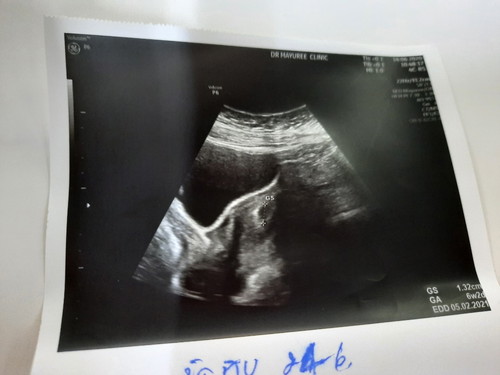

อัลตราซาวนด์ไม่พบเด็ก

เพิ่งตั้งครรภ์ได้ 6 สัปดาห์เวลาไปอัลตราซาวนด์จะเจอน้องมั้ยคะ วันนี้ไปอัลตราซาวแต่ไม่ชัดคะ

บ้านนี้ซาวด์ 6week ยังไม่เจอค่ะ มาเจอตอน 7w6d ค่ะ

บ้านนี้เจอหัวใจตอน 7 w ค่ะ ยังไม่เปนตัวเลย

โอเครค่ะ เป็นกังวลมากเพราะคนแรกเจอถุงตั้ง4สัปดา